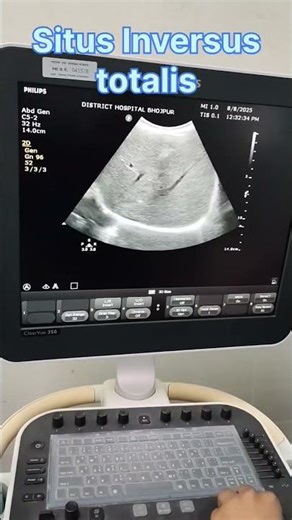

Top suggestions for Situs inversus |

Echo - Dextrocardia Situs Inversus

Echocardiography - Hitman

Situs Inversus - Situs

Dewasseabv - Situs